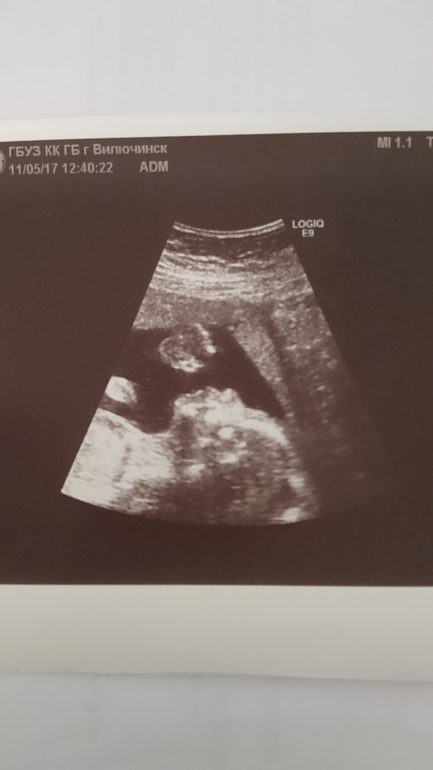

Сын.

Второй скрининг пройден. У нас мальчик :) Смешанные чувства. До сих пор не могу привыкнуть, что беременна. А тут уже и пол сказали.. :) Время летит. У нас всё хорошо. Пинаемся с 20 недели. Всякие щекотки, порхание бабочки я пропустила :) Сразу начались отчётливые толчки. Ну а что, мужик же :) Не размениваемся на мелочи.

Дали фото. Муж сказал, что профиль точно его. Особенно нос